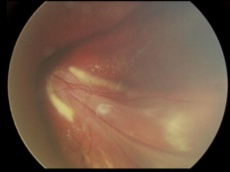

Retinal capillary hemangioma with prominent retinal feeder vessels[26] |

Choroidal melanoma fundus photo and B scan. This tumor was initially treated as choroidal hemangioma. [30] |

PEHCR in temporal quadrant of OD. Left: before treatment with anti-VEGF (left); Right: 4 months after anti-VEGF[31] |